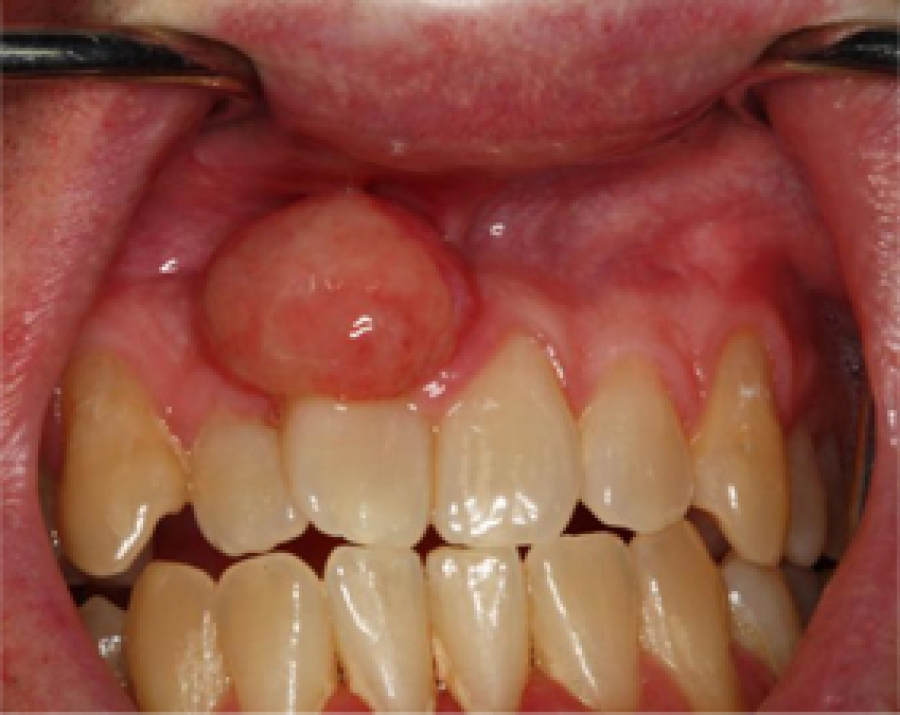

პირის ღრუს კისტები

მიუხედავად ამისა, საშიშია, ვინაიდან შეუძლია, სრულიად დაშალოს ყბის ქსოვილი და მძიმე დაავადებების მიზეზად იქცეს. როგორ აღმოვაჩინოთ და ვუმკურნალოთ კისტებს? ამაზე შპს #1 სტომატოლოგიური პოლიკლინიკის ქირურგი თინა ჩრდილელი გვესაუბრება.

- ყველაფერი პერიოდონტიტიდან (კბილის ფესვსა და ყბის ძვალს შორის მდებარე თხელი ქსოვილოვანი შრის ანთებიდან) იწყება. ანთების შედეგად კბილის ფესვის ირგვლივ ქსოვილები ჩაიზრდება და ახალწარმონაქმნი ვითარდება. როცა ახალწარმონაქმნი 5 მმ-მდე ზომისაა, მას გრანულომას ვუწოდებთ, ამაზე დიდი კი უკვე კისტაა. ეს კისტები რადიკულურია და პირის ღრუს ყველაზე მეტად გავრცელებულ სიმსივნურ წარმონაქმნებს წარმოადგენს. ისინი სხვადასხვა ასაკის ადამიანებს უჩნდება, თანაც ზედა ყბაზე სამჯერ უფრო ხშირად, ვიდრე ქვედაზე.

დროთა განმავლობაში კისტა იზრდება, გარსით იფარება და ყბის ძვალში წარმოქმნის ტომსიკს დაზიანებული უჯრედებისა და მიკროორგანიზმების შემცველი ნახევრად თხიერი შიგთავსით. ამ დროს ადამიანი ვერაფერს გრძნობს, რადგან ავადმყოფი კბილი ჯანმრთელისგან გარეგნულად არაფრით განსხვავდება. ღრძილიც ერთი შეხედვით ჯანსაღია. ერთადერთი, შესაძლოა მყარი საკვების ღეჭვისას წარმოიქმნას უსიამოვნო შეგრძნებები და ისიც - ყოველთვის არა.